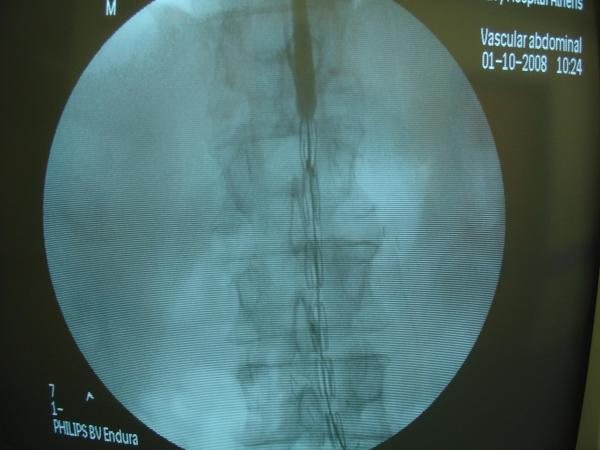

Endovascular repair of anastomotic abdominal aortic aneurysm, after aortobifemoral bypass

Vascular Clinic, Naval and Veterans Hospital of Athens

AVEM2009-Thessaloniki